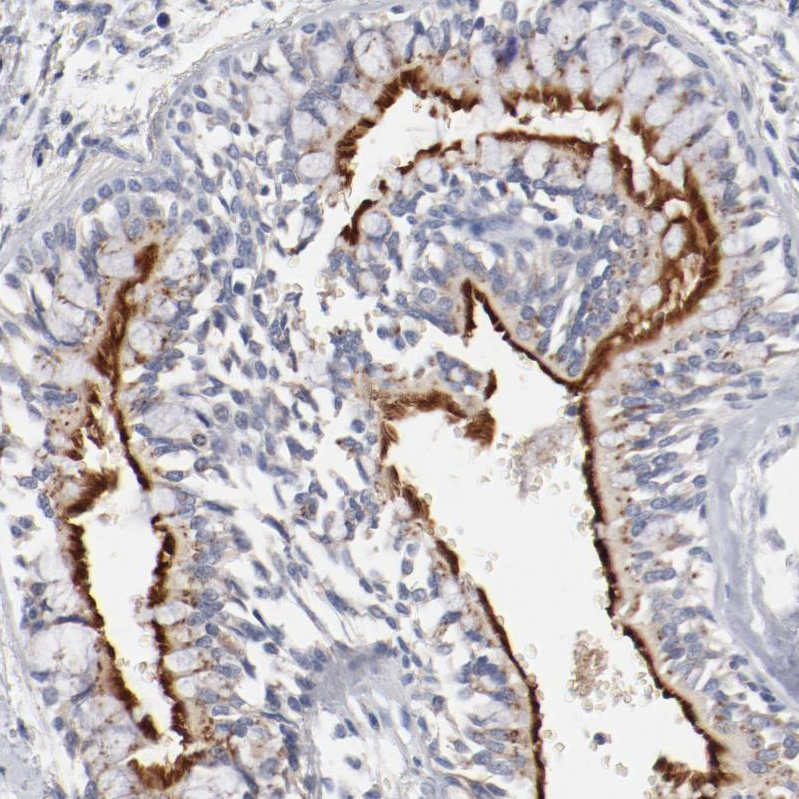

Immunohistochemistry analysis in human fallopian tube and lymph node tissues using HPA003543 antibody. Corresponding AK7 RNA-seq data are presented for the same tissues.